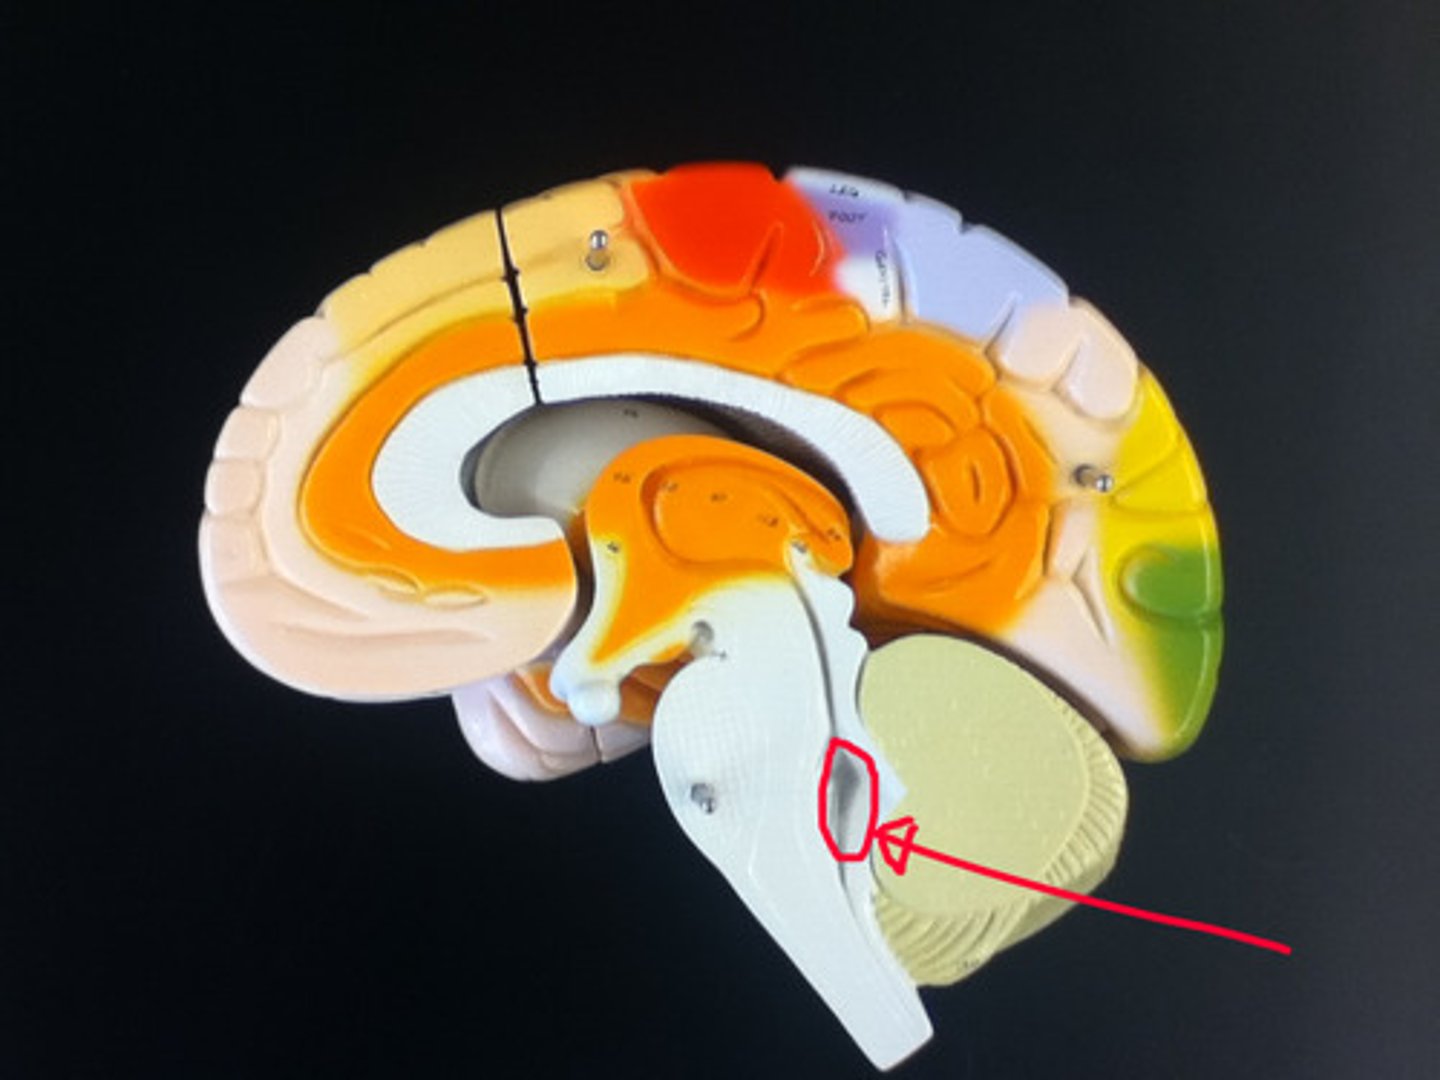

MIdsagittal View of brain

Lateral Ventricle

Third Ventricle

Cerebral Aqueduct

Forth Ventricle

Corpus Callosum

Fornix

Thalamus

Pineal Gland

Superior Colliculi

Inferior Colliculi

Midbrain

Hypothalamus

Caudate Nucleus

Globus Pallidus

Putamen

Choroid Plexus